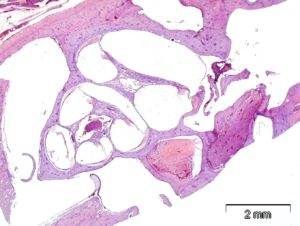

–Histopathology-beautiful cochlea on right